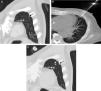

(A) MIP (maximum intensity projection) oblique coronal CT image of the chest in which 2 small opacities measuring <1cm are seen in the left upper lobe: a larger (white arrow) and another smaller lesion (black arrow). (B) MIP axial CT image of the chest showing the moment in which the seed was released from the 18G trocar needle. (C) MIP oblique coronal CT image of the chest confirming the correct equidistant placement of the I-125 seed (curved arrow) between the 2 lung lesions (straight arrows).

This was a 65-year-old patient with rectal cancer, in whom pulmonary metastases were detected on radiological monitoring of his disease. After adjuvant treatment with chemotherapy, the lung nodules disappeared, with the exception of 2 small pseudonodular opacities measuring less than 1cm in the left upper lobe, only 22mm apart (Fig. 1A). A multidisciplinary committee decided to perform image-guided percutaneous marking for subsequent resection by VATS. The initially agreed procedure was to place 2 markers (1 for each pseudonodular opacity) under CT guidance. However, given the relative proximity of the 2 pulmonary opacities and the possibility of causing pneumothorax after placement of the first marker that would prevent the release of the second, we decided to place a single marker (a low-radiation radioactive I-125 seed) equidistant between the 2 lesions. The percutaneous release of the marker was uneventful, and the seed was deposited at a distance of 11mm from each nodule (Fig. 1B and C). One week later, the patient underwent CT-guided VATS, and both lesions were successfully removed with a pulmonary wedge resection.